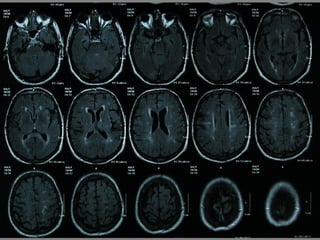

Un paciente de 75 años ingresó en el hospital debido a síntomas neurológicos como bradipsiquia, disartria y torpeza motora en las extremidades derechas que habían estado presentes durante las últimas 12 horas. Tenía antecedentes de fibrosis pulmonar e infección respiratoria reciente. El examen reveló disartria leve, paresia facial central derecha y claudicación en las extremidades derechas, lo que sugiere un posible ictus en el hemisferio izquierdo.